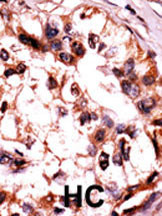

Formalin-fixed and paraffin-embedded human cancer tissue reacted with the primary antibody, which was peroxidase-conjugated to the secondary antibody, followed by AEC staining. This data demonstrates the use of this antibody for immunohistochemistry; clinical relevance has not been evaluated. BC = breast carcinoma; HC = hepatocarcinoma. |